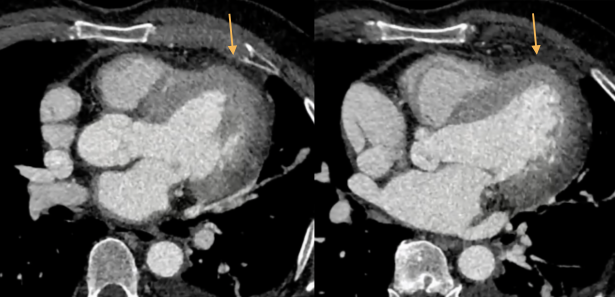

- Risque: Hernie du VG ou autres structures cardiaques à travers l’agénésie partielle → Compression des coronaires et ischémie (MORT SUBITE)

- TTT opératoire avec Patch Péricardique